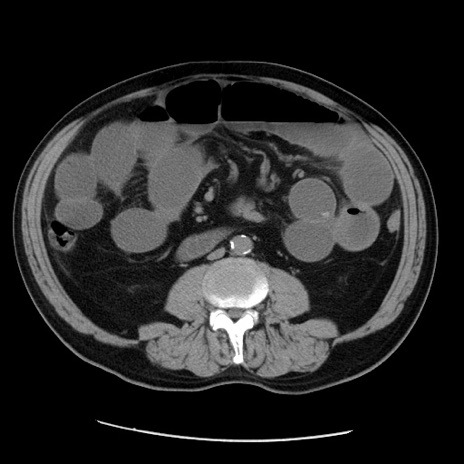

症例20(横断像)

【症例】 60歳代男性

【主訴】 腹部膨満、嘔吐

【現病歴】5日前頃より倦怠感を認め食事量減少し4日前の朝嘔吐、食事摂取困難となった。 3日前近医受診し点滴施行され整腸剤などを処方された。 当日他院を受診し、腹部膨満著明、炎症反応の上昇(CRP10.8、WBC11200)あり、紹介受診となる。

【身体所見】 意識JCS1 受け答えがはっきりしないBP 111/57mHg、 P 67bpm、、BT35.2°C、SpO2 97%(RA)、 腹部:膨隆、打診で鼓音あり、全体的に圧痛有り、腸蠕動音(-)、反跳痛ははっきりせず。

【データ】WBC 11400、CRP 14.20